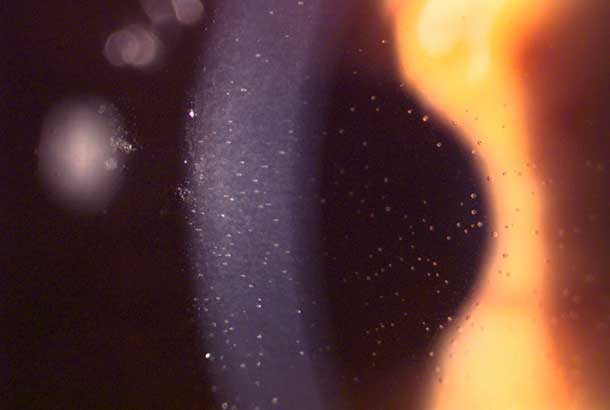

"detail": "<h2>Symptoms</h2>\n\n<ul>\n\t<li>None</li>\n</ul>\n\n<h2>Signs</h2>\n\n<ul>\n\t<li>Variation in cell size and cell shape (pleomorphism) of the endothelium; seen with high magnification (40x) in the endothelial specular reflection</li>\n</ul>\n\n<h2>Etiology</h2>\n\n<ul>\n\t<li>Thought to result from chronic hypoxia causing corneal acidosis following wear of lens with a low Dk/t</li>\n\t<li>Common in long-term wearers, especially of PMMA and low Dk/t hydrogel lenses</li>\n</ul>\n\n<h2>Prevalence</h2>\n\n<ul>\n\t<li>Rare with modern materials</li>\n</ul>\n\n<h2>Differential Diagnosis</h2>\n\n<ul>\n\t<li>Other&nbsp;<a href=\"/condition/62\">endothelial anomalies</a>&nbsp;and corneal dystrophies</li>\n\t<li>See: <a href=\"/condition/62\">Endothelial Changes &ndash; Differential Diagnosis</a></li>\n\t<li><a href=\"/condition/61\">Corneal Exhaustion Syndrome</a></li>\n</ul>\n\n<h2>Management</h2>\n\n<ul>\n\t<li>Refit with a lens of high Dk/t (SiHy), or change to DW / reduce wearing time</li>\n</ul>",